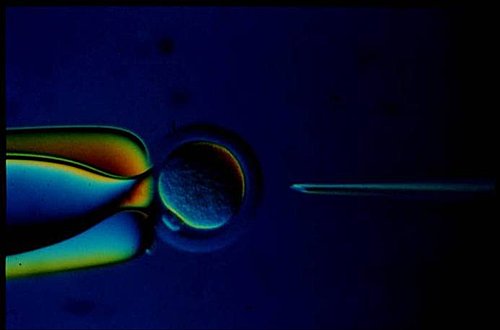

在面對傳宗接代的壓力下,我進一步詢問江醫師,沒有輸精管是否還有「子」望?他告以最近北醫引進副睪丸取精術,可藉手術把副睪丸切開,吸取精子再進行體外受精,這種技術在美國已率先宣佈「做人」成功。不過,他也強調,取自副睪丸的精蟲品質較不成熟、活動力差、數量不多,除了在人工取精需要純熟的技巧外,人工助孕多少還得靠些運氣。另外,該手術還需要配合內人排卵時間取卵,再把受精卵植入子宮,過程麻煩,所以要我回家考慮、考慮。

為了擁有下一代,妻和我都決定忍受一刀之苦,毅然接受這項在國內尚屬先進的人工生殖技術。那天一早,我倆同時身處手術房,內人在曾醫師精細的取卵技術下,取下十二顆卵子,隔床的我則在江醫師妙手之下,從副睪丸取出約十五萬隻精蟲,經過篩選洗滌後,立刻進行人工受精;再一個半小時的鎮靜處理時間內,雖然一切渾然不知,卻是有生之年感覺最漫長、難挨的時刻。